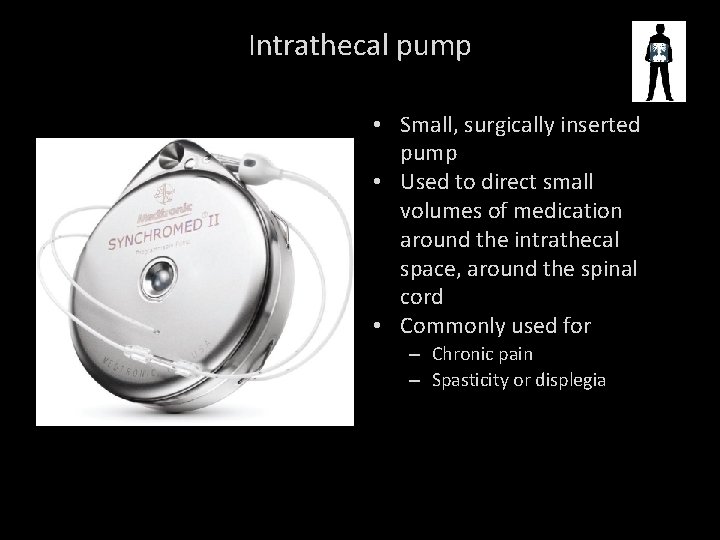

Intrathecal pump • Small, surgically inserted pump • Used to direct small volumes of medication around the intrathecal space, around the spinal cord • Commonly used for – Chronic pain – Spasticity or displegia